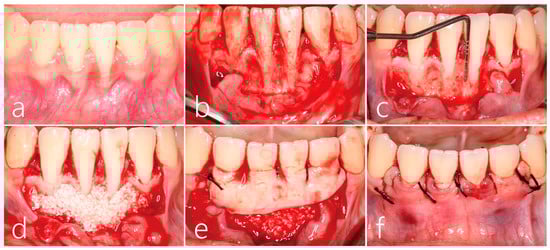

2. Case Report